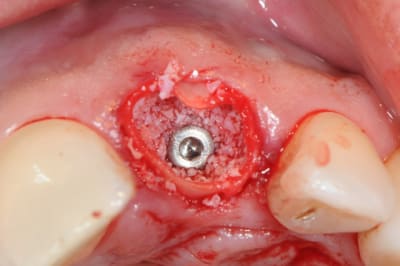

ROG dans un autre style mais quasiment les mêmes produits, Genos à la place du MP3 (pareil avec moins de collagène) et meme membrane.

Sur scan avant extraction, on voit la persistance d'une corticale vestibulaire en cervical mais une perforation de celle-ci en apical.

La corticale cervicale semblant très fine et la patiente ayant un sourire gingival, j'ai choisi d’extraire et de faire un ROG pour conserver ce volume osseux en vestibulaire, avant d'implanter plus tard.

technique décrite par Tarnow: très simple à réaliser, le résultat me convient tout a fait.

Désolé mais pas de photos de la pose de l'implant (réalisée 6 mois après ROG-extraction) mais très bonne sensation au forage et aspect "os vivant".

désolé mais les scan sont pas dans l'ordre mais je ne sais pas comment le modifier.